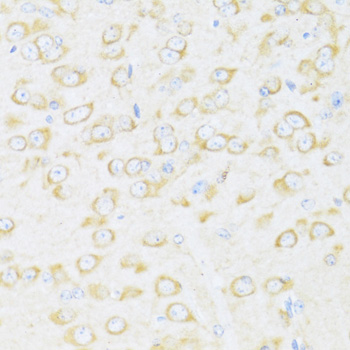

Immunohistochemistry of paraffin-embedded rat brain using DDX3Y antibody at dilution of 1:100 .

Immunohistochemistry of paraffin-embedded mouse brain using DDX3Y antibody at dilution of 1:100 .